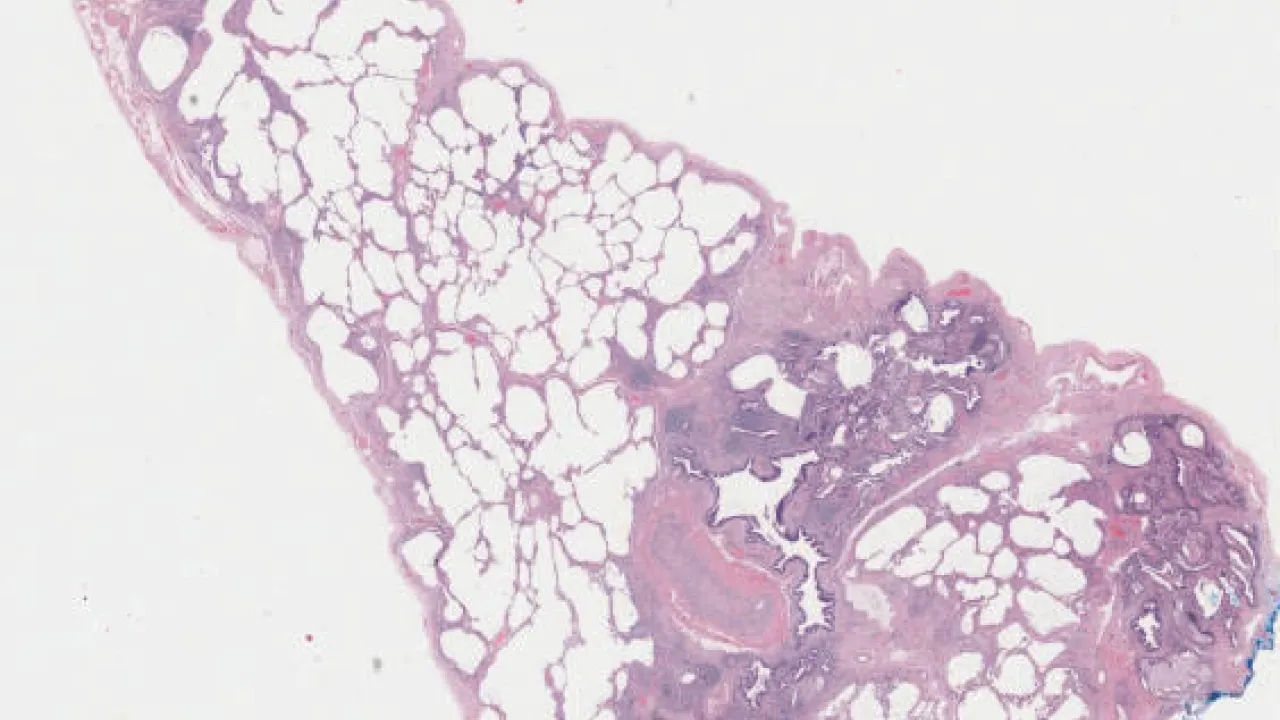

Lung

Lung, surfactant dysfunction disorder

Lung, Usual interstitial pneumonia

Lung, Cryptogenic organizing pneumonia

Lung, Chronic eosinophilic pneumonia

Lung, Nonspecific interstitial pneumonia, cellular pattern